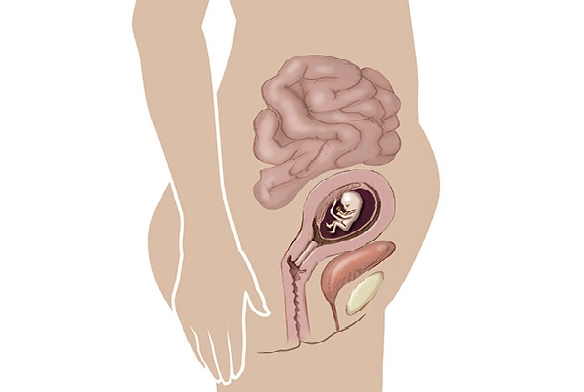

في الأسبوع الحادي عشر من الحمل، يبلغ طول جنينكِ حوالي ٤١ ميليمتراً أي بحجم ثمرة تين صغيرة!

لا يزال رأسه أكبر من جسمه، ولكن الأطراف والجسم ينموان بسرعة ملحوظة. تبدأ أصابع اليدين والقدمين بالانفصال، وتتكوّن الأظافر الصغيرة، وتبدأ الأذنان بالتحرك إلى موقعهما الطبيعي على جانبي الرأس.

إنه أسبوع حافل بالنمو السريع والتطور العصبي للجنين، وفي المقابل يواصل جسمكِ التكيف مع هذه المرحلة المميزة من الحمل.

👶 تطوّر الجنين في الأسبوع الحادي عشر من الحمل